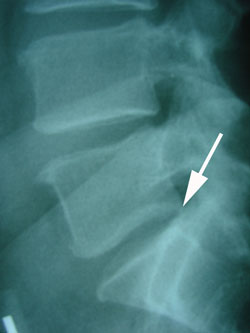

The stress on the intervertebral disc as the backward movement of the vertebra occurs creates much stress on the disc which then causes back pain. (See the white arrow for retrolisthesis.)